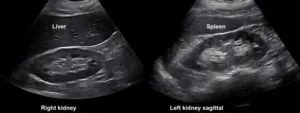

A 53 year old man with heart failure with reduced ejection fraction (~37%) secondary to non-ischemic cardiomyopathy and end-stage kidney disease (ESKD) recently initiated on hemodialysis underwent a right upper quadrant ultrasound for elevated liver function tests. Despite a radiology report indicating “normal liver morphology and hemodynamics,” a review of images by the nephrology team revealed severe venous congestion. This was evidenced by a dilated inferior vena cava (IVC) with an approximate anteroposterior diameter of 3 cm, systolic (S-wave) reversal in the hepatic vein flow, and a pulsatile portal vein with some flow reversal (Figure 1). These sonographic findings are consistent with VExUS grade 3 (Figure 2).

Figure 1. Radiology-performed scan images demonstrating a dilated inferior vena cava (approximately 3 cm), S-wave reversal on hepatic vein Doppler and a pulsatile portal vein (below-the-baseline blebs represent flow reversal).